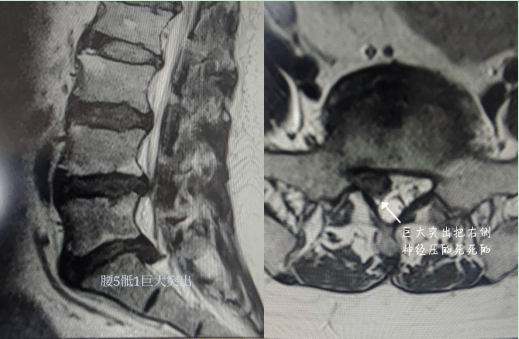

MRI显示L5S1椎间盘巨大突出

压迫右侧神经根